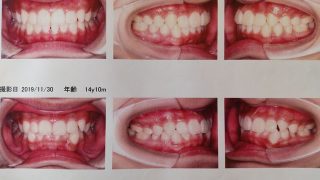

矯正

《とり》の矯正が一旦経過観察になりました。毎週マウスピースを新しい物に変えていき、ここまできれいになりました。噛み合わせが深かったのも改善されました。ワイヤーの矯正より値段は高いですが、歯磨きなどはしやすかったようです。